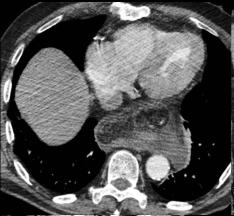

Meme cas en coupe TDM axiale |